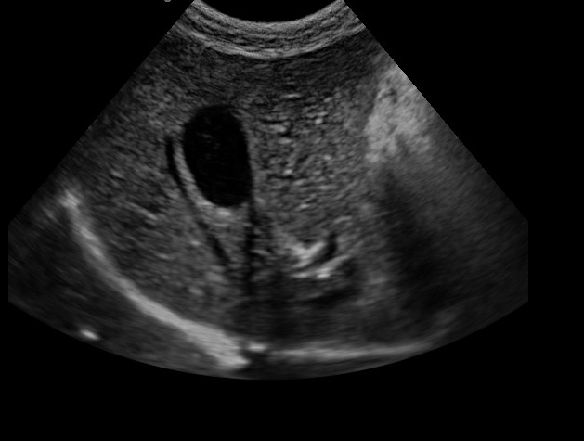

·顯示模式:B、B+B、4B、B+M、M、PW

·適用于各種動物的臨床腹部、胸腔,心臟、肌腱、小器官、眼球、生殖系統等的檢查